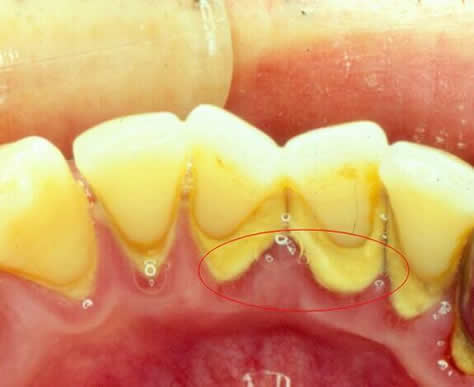

牙结石是指附着在牙齿表面的钙化块。它是在牙齿表面的牙菌斑基础上,由唾液中矿盐沉积逐渐钙化而形成的。

钙化发生于钙离子与牙菌斑的细胞间有机物质蛋白质——多糖复合物结合,然后磷酸钙晶体沉积于细胞间物质与细菌上。钙化是沿着牙菌斑附着牙面的内侧发生、持续进行的,大约数月后达到极点,由于咀嚼食物、舌颊压力等原因,牙结石不会无限制地沉积。